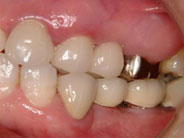

7年前に右下顎にインプラントを入れました。

入れ歯に較べて、人生が変わるほど何でも食べられる、と喜んでいただいています。

X線的にも何の問題も無く経過しており、平気で10年持ちそうです。